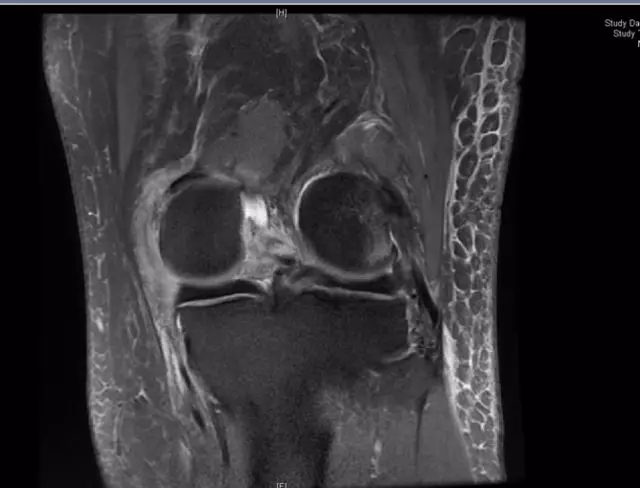

后交叉韧带断裂

这个病例韧带连续性中断松弛,尤其上止点的信号增高;从这个层面来看它的上止点形态不完整,部分信号增高;从这个层面可以看到,韧带的形态信号增粗,松弛,信号也是增高的,所以这个病例可以诊断为后交叉韧带断裂。